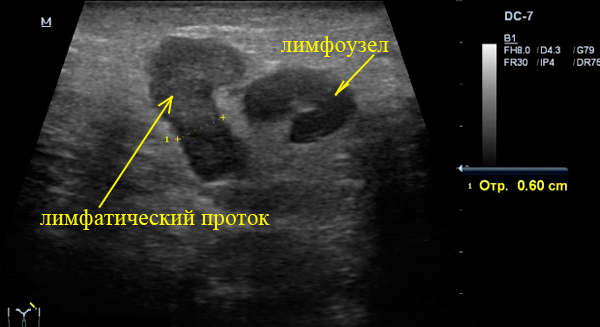

Написал заключение - Левосторонний паховый лимфаденит с лимфангитом.

На самом деле лимфоузлов здесь не так и много, в основном визуализируются расширенные лимфатические протоку - лимфангит.

Лимфоузел